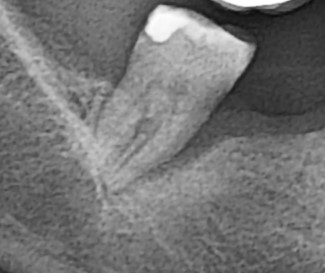

1. Κλινική εικόνα δοντιού με περιοδοντική νόσο. Διακρίνεται αιμορραγία και υποχώρηση των ούλων.